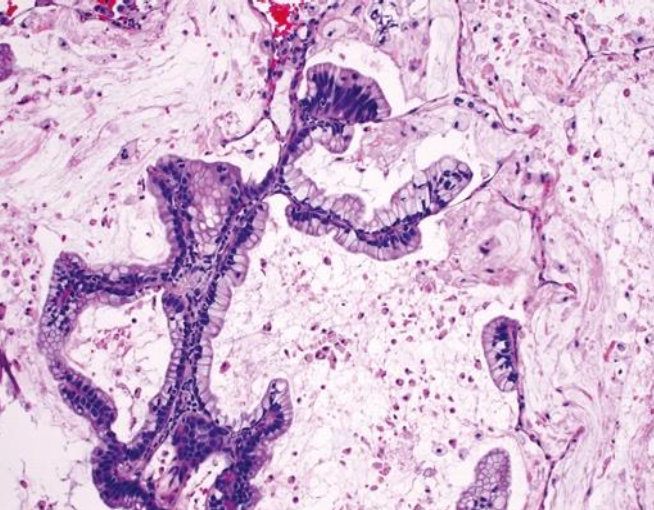

<p>Mesotelioma epiteloide</p>

Mesotelioma epiteloide

Parece adenocarcinoma: diferenciador

• Calretinina, WT-1 CK5/6 positivos